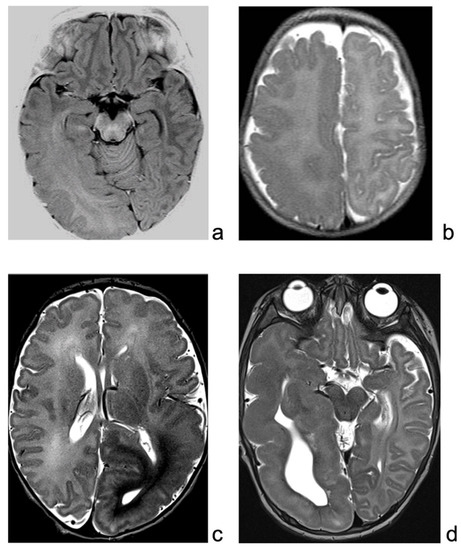

4.1. Patient #1

4.2. Patient #2

4.3. Patient #3

4.4. Patient #4

| 1 | 0.3 | 1.5 | GVG | Right HME | Asymmetric spasms (left) | Continuous spikes/polyspikes and slow waves, with low voltage fast activity over the right hemisphere. | Engel Ia | 11 | Hydrocephalus |

| 2 | 0.5 | 2.9 | PB, ACTH, VPA, GVG, CLB, LEV | Right HME | Left tonic seizures and asymmetric spasms | Continuous periodic paroxysmal activity over the right posterior perisylvian region. | Engel Ia | 7 | Hydrocephalus |

| 3 | 0.1 | 0.3 | PB, GVG, ACTH, CBZ | Left HME | Right asymmetric spasms and tonic seizures | Pseudo-periodic paroxysmal pattern over the left hemisphere, mainly over temporal and parietal regions. | Engel Ia | 5 | No |

| 4 | 0.1 | 0.2 | VGB, PB, LEV | Right HME | Left clonic seizures | Continuous slow delta waves over the right occipital area, sometimes diffused over the homologous contralateral area. | Engel Ia | 5 | Left transverse venous sinus thrombosis. |